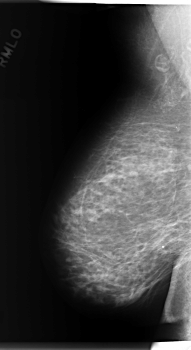

C_0280_1.RIGHT_MLO

ics_version 1.0

filename C-0280-1

DATE_OF_STUDY 30 12 1994

PATIENT_AGE 50

FILM_TYPE REGULAR

DENSITY 2

DATE_DIGITIZED 2 6 1998

DIGITIZER LUMISYS LASER

RIGHT_CC LINES 5888 PIXELS_PER_LINE 3152 BITS_PER_PIXEL 12 RESOLUTION 50 NON_OVERLAY

RIGHT_MLO LINES 5944 PIXELS_PER_LINE 3240 BITS_PER_PIXEL 12 RESOLUTION 50 NON_OVERLAY